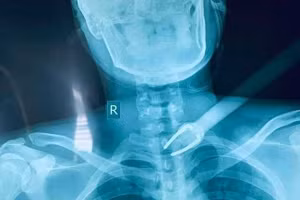

"Báo động đỏ" cứu sống nam sinh viên bị kẻ trộm bắn mũi tên xuyên cổ 09/02/2021 12:21 GD&TĐ - Theo bác sĩ Bệnh viện Đa khoa (BVĐK) Trung tâm An Giang, BV vừa phẫu thuật cứu sống nạn nhân là nam sinh viên bị kẻ trộm dùng nỏ tự chế bắn một mũi tên vào ngay vùng cổ.